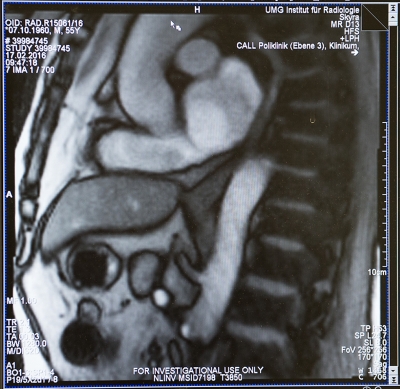

Das Göttinger Forscherteam nutzt dafür das Verfahren der Magnetresonanz-Tomografie (MRT) in Echtzeit. Mit Hilfe dieser Technik, der sogenannten „Echtzeit-MRT“, kann der Schluckakt mit 25 Bildern pro Sekunde dokumentiert und untersucht werden. Das Echtzeit-MRT liefert Bilder, die für diagnostische Zwecke in der Klinik und für die Behandlung nutzbar sind. Ursachen von Sodbrennen oder Schluckstörungen lassen sich genauer erkennen und untersuchen. Für eine individuelle und gezielte Behandlung der Volkskrankheit Sodbrennen eröffnen sich damit neue Wege.

Die Echtzeit-MRT liefert Bilder, mit denen der Schluckvorgang vom Mundraum durch die Speiseröhre bis zum Mageneingang verfolgt werden kann. Auch der Reflux, der entscheidende Akt für Sodbrennen, lässt sich unmittelbar beobachten: Um den Eintritt von Magensäure in die Speiseröhre auszulösen, reicht eine einfache Pressung auf den Bauch des Patienten. „Auf diese Weise lässt sich Sodbrennen diagnostizieren. Gleichzeitig können wir auch die anatomische oder funktionelle Veränderung entdecken, die dem Sodbrennen zugrunde liegt. Wir können jetzt ganz genau sehen, was die Ursache ist: Das kann eine verzögerte Muskelbeweglichkeit (Peristaltik) der Speiseröhre sein oder eine Störung des Übergangs von der Speiseröhre in den Magen oder eine Entleerungsstörung des Magens in den Darm“, so Priv.-Doz. Dr. Beham.